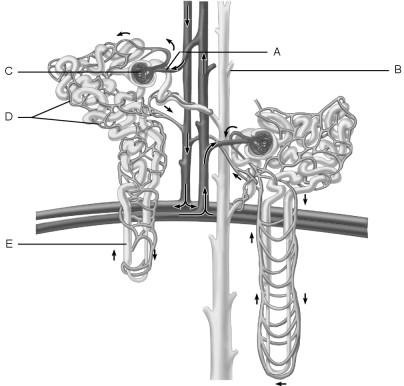

Afferent arteriole.

A

In the kidneys, the countercurrent mechanism involves the interaction between the flow of filtrate through the nephron loop of the juxtamedullary nephrons (the countercurrent multiplier) and the flow of blood through the limbs of adjacent blood vessels (the countercurrent exchanger). This relationship establishes and maintains an osmotic gradient extending from the cortex through the depths of the medulla that allows the kidneys to vary urine concentration dramatically.

TRUE or FALSE

TRUE

Cells that are most affected by ADH.

C

Medulla of the kidney.

E

Glomerulus.

C

Is composed of simple squamous epithelium.

A